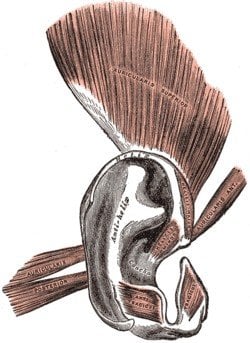

5. Ear Muscle

The Auriculares muscles are used by creatures to control their external ears without actual moving the head. This helped in focusing their hearing onto certain sounds. As primates, we had the ability to swivel our pinnas (external ear) to augment our peripheral hearing, like a cat, albeit not to the same extent. All we can do now is make them wiggle, unless you are Mr. Bean, who is probably closer to a chimp than a human on the evolutionary scale anyway.